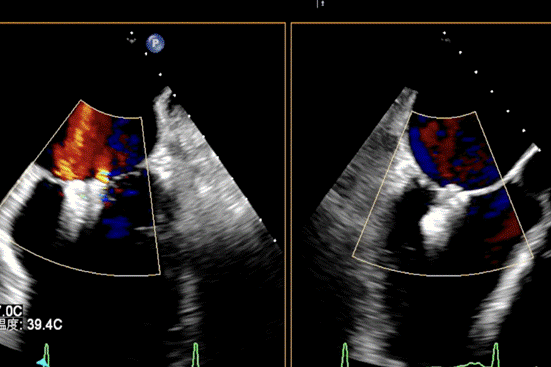

患者全麻成功后,经右股静脉建立路径,穿刺房间隔,瓣膜夹通过输送系统送入左心房,顺利到达病变二尖瓣区域。在经食道超声和DSA的辅助下,通过反复评估二尖瓣返流位置、抓捕位置、返流程度,最终在A2P2位置植入一枚DragonFly™夹子。手术操作时长48分钟,透视时间总计为5分钟,术后患者无不适感,整个手术流畅完美,患者返流程度降至微量。

患者全麻成功后,经右股静脉建立路径,穿刺房间隔,瓣膜夹通过输送系统送入左心房,顺利到达病变二尖瓣区域。在经食道超声和DSA的辅助下,通过反复评估二尖瓣返流位置、抓捕位置、返流程度,最终决定在A2P2位置植入俩枚DragonFly™夹子,显著改善了患者的返流情况。手术操作时长60分钟,透视时间总计为15分钟。术后患者无不适感,整个手术流畅完美,患者返流程度从重度降至轻度。